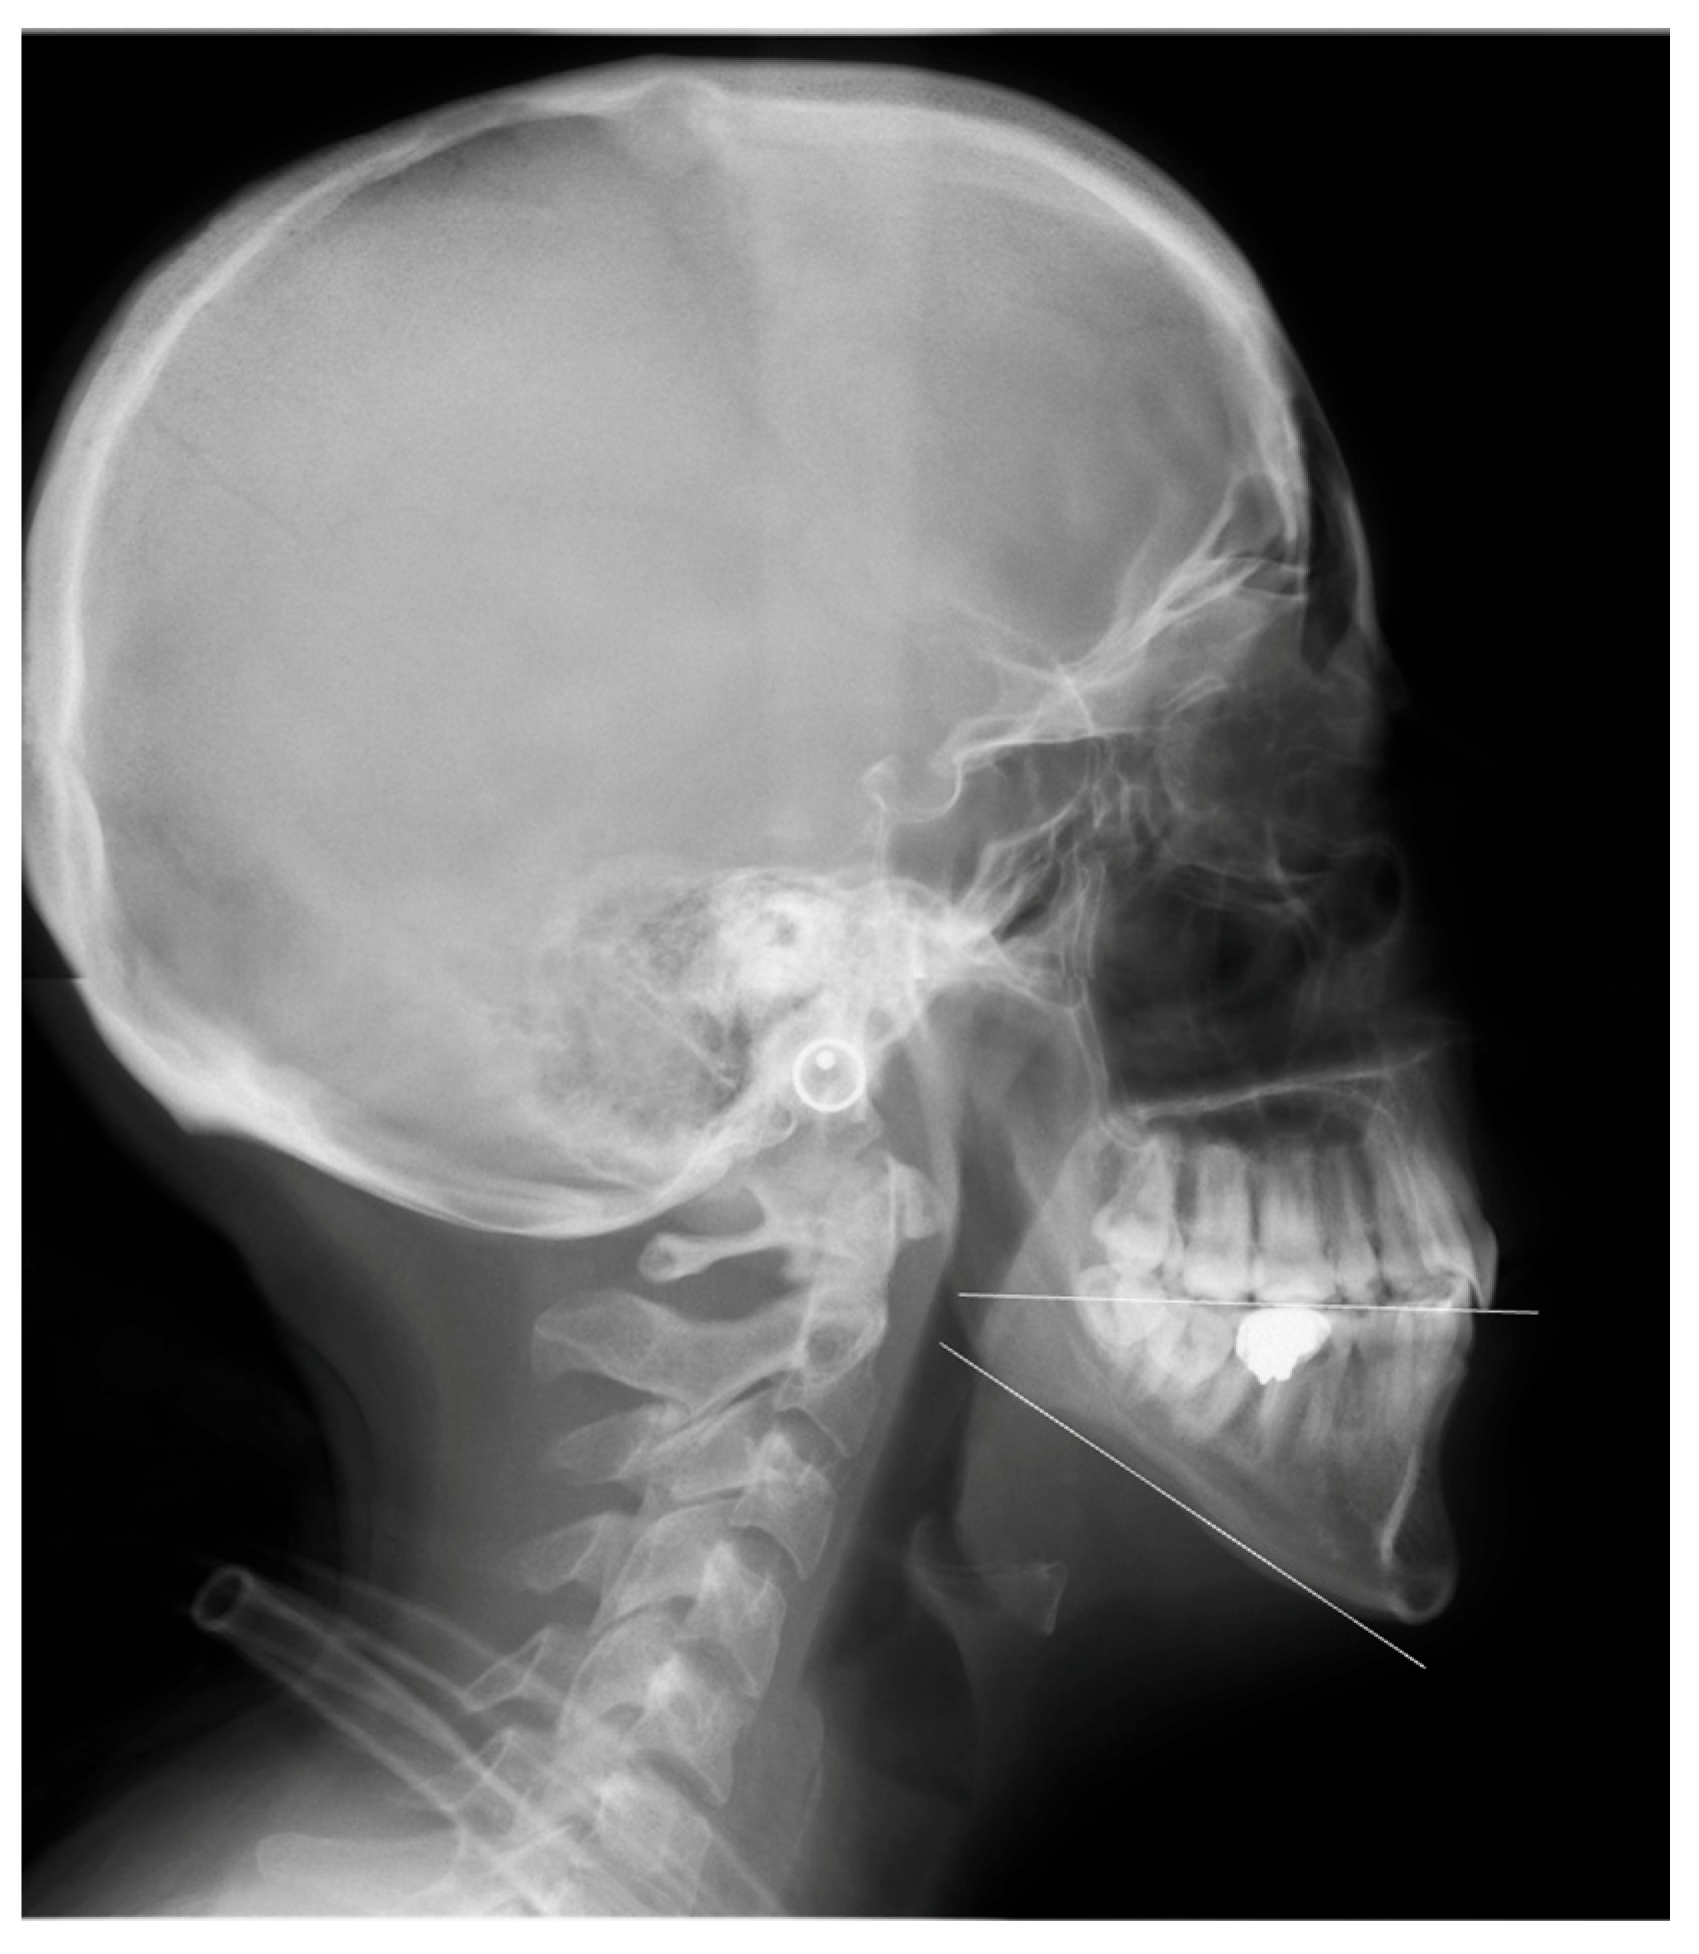

Optimizing Maxillomandibular Position in Orthognathic Surgery: Introducing the T Concept in Treatment Planning

2. The T Concept

3. The Chin Rationale

4. Step-by-Step Planning

4.4. Phase-Four (T Concept)